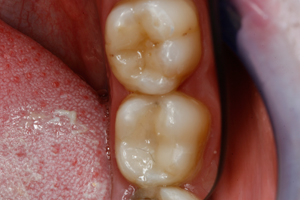

Thank you to our patients that have allowed us to show examples of our work

Have a look at just some of the many patient examples we have captured from BEFORE and AFTER their treatments and cosmetic surgeries.

From Whitening to Veneers, Fillings to Cosmetic Teeth Makeovers, here are some examples of the work that Dr. Dadabhai has provided to his patients to give them a more confident smile and a positive, pain free feeling.

Slide your computer mouse or finger (touch screens) over the image to view BEFORE and AFTER comparison.